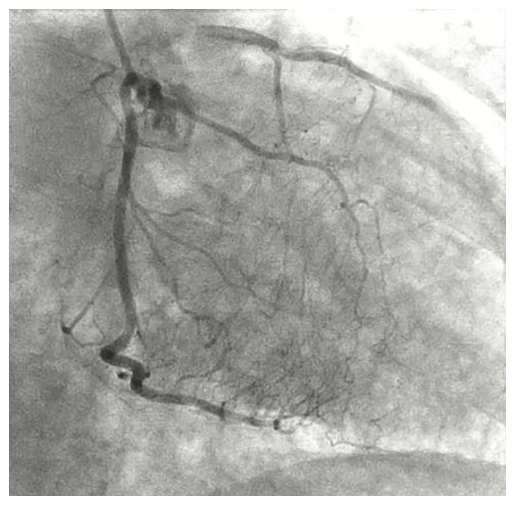

A 54-year-old female with a history of peripheral arterial disease (PAD), tobacco abuse, diabetes, severe chronic obstructive pulmonary disease (COPD), obesity, hypertension, and hyperlipidemia presented to an outside hospital with a non-ST-elevation myocardial infarction (NSTEMI). Subsequent left heart catheterization revealed a chronic total occlusion (CTO) of the left anterior descending coronary artery (LAD) and left circumflex (LCx), with a 95% ostial ramus and a patent right coronary artery (RCA) with right to left collaterals (Figures 1-2). Initial ejection fraction by ventriculogram was approximately 30-35%. She was turned down for surgery and subsequent studies revealed viable myocardium; therefore, she was scheduled for percutaneous revascularization with mechanical circulatory support using an Impella left ventricular assist device (Abiomed). She was found to have bilateral occlusion of her iliac stent (Figure 3). It was decided to revascularize at least one of her occluded iliac arteries, and then use the femoral and radial approach for dual access in order to recanalize the CTO. The axillary artery would be used for the Impella, rather than advancing the 14 French (Fr) sheath through a freshly stented artery. The right iliac artery was revascularized and she was brought back to revascularize the left system.